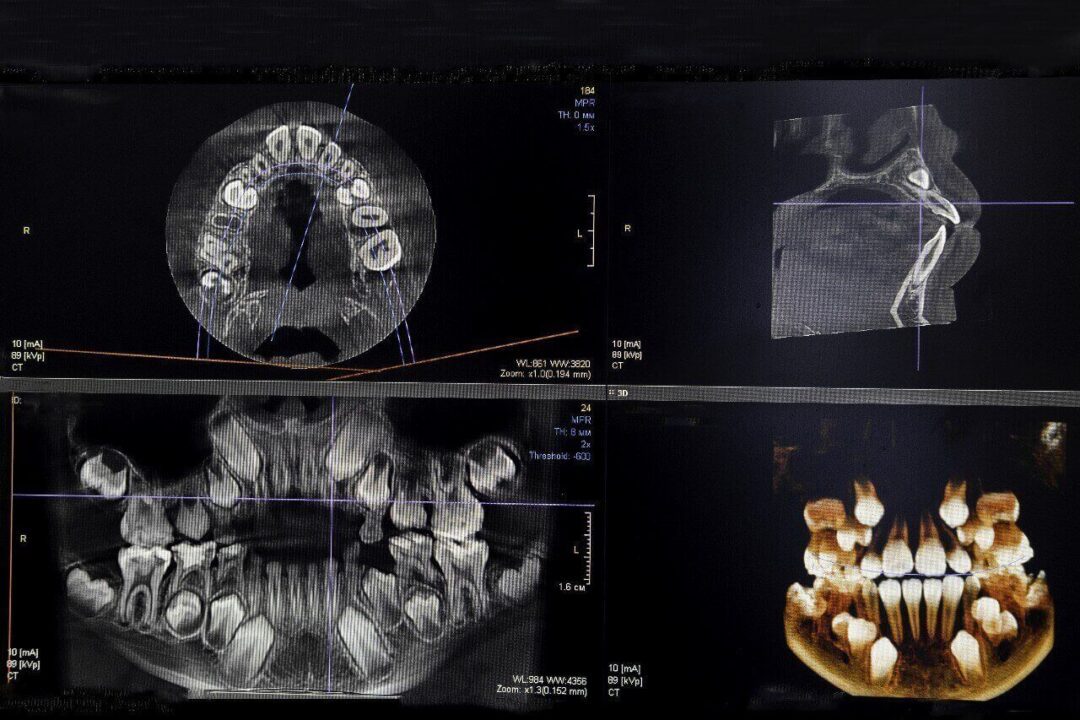

الأشعة البانورامية والأشعة المقطعية مركز عمارة للاسنان Panoramic X-rays and CT scans , Raggi X panoramici e scansioni TC

2. التصوير المتقدم: استخدام تقنيات أشعة متقدمة (كالأشعة ثلاثية الأبعاد أحياناً) لتقييم حالة العظم والجذر.

الأشعة البانورامية والأشعة المقطعية -

• الأشعة المقطعية ثلاثية الأبعاد (CBCT): تُعد هذه التقنية ثورة في طب الأسنان، حيث توفر صورة مفصلة ثلاثية الأبعاد للفكين، الأنسجة الرخوة، الأعصاب، والجذور. هذا يسمح للطبيب بتقييم دقيق لحالة العظم حول السن المصاب، وتحديد مدى عمق الكسر، وكيفية تعامل حشو العصب مع القنوات المعقدة. هذه الدقة هي مفتاح النجاح في إنقاذ الأسنان.